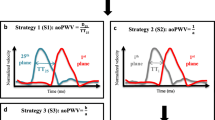

As previously described [31], to minimize the variability of foot-to-foot measurement inherent to lower temporal resolution on mean velocity curves compared to pressure curves, the transit time (Δt) was calculated automatically using a method based on the least squares minimization approach between the systolic up-slope of the ascending aorta mean velocity curve, and the whole descending aorta mean velocity curve. The systolic up-slope was defined as the portion of the mean velocity curve comprised between the onset of the blood flow and the time of its maximum. This up-slope portion was preferred to the entire flow curve because of the unidirectional and reflectionless nature of the flow wave during this systolic phase as shown in [16, 26].

First, the mean velocity waveforms were re-sampled to a temporal resolution of 1 ms using a cubic interpolation, and were normalized to account for the differences between the waveform amplitudes. Then, the transit time (Δt) was calculated as the time shift for which the resemblance between the profile of the systolic up-slope of the normalized mean ascending aorta velocity waveforms (), and the normalized descending aorta waveform (E D ) was maximal. This maximal resemblance was obtained by shifting E D by successive temporal translations with a unitary step of 1 ms, and by minimizing the quadratic error (Er) between and E D .

The transit time Δt was then provided as follows: